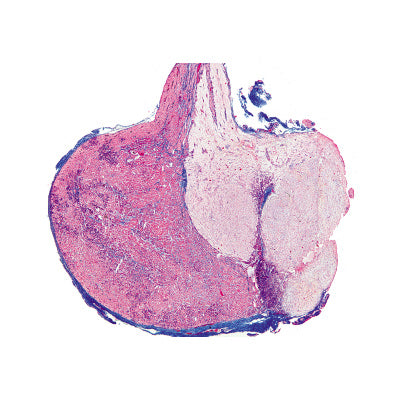

1(d). Ovary of cat, with follicles and corpus luteum t.s.